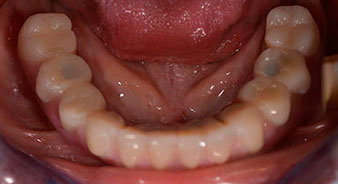

Dopo aver illustrato alla paziente le varie opzioni di trattamento disponibili, la donna ha preferito scegliere l'estrazione della dentatura residua dalla mandibola, procedendo poi all'implantologia immediata e al trattamento con il metodo Fast & Fixed (Bredent medical). In questo caso, la protesi fissa provvisoria viene innestata su quattro impianti lo stesso giorno dell'intervento. L'obiettivo è quello di operare la paziente il venerdì, permettendole di essere presente agli esami orali il lunedì seguente.

È stata eseguita una tomografia computerizzata Dentale Cone Beam in 3D (CBCT, con Planmeca) per aiutare la programmazione dell'intervento e la riduzione di rischi. L'esame ha evidenziato che la qualità e quantità dell'osso disponibile era sufficiente per eseguire l'intervento e la ricostruzione immediata, utilizzando il metodo Fast & Fixed. In base al protocollo del sistema, gli impianti sono stati inseriti in posizione 35, 32, 42 e 45. Gli impianti distali vengono installati a un angolo massimo di 45 gradi. Così facendo, il profilo che ne risulta viene spostato in posizione posteriore, generando un poligono di supporto più ampio (Fig. 3).